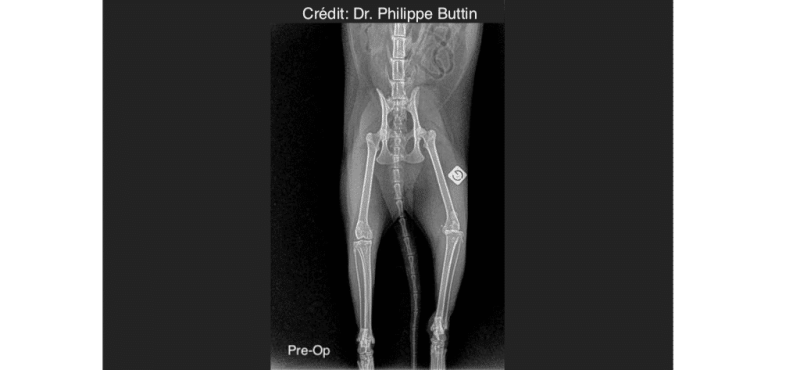

Radiologické snímky